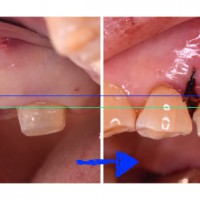

歯がないまま放置したために、反対の歯が出てきてしまったとき。(歯冠長延長術・クラウンレングスニング)

こんにちは。 今回は、長年歯を失ったまま放置してしまったために、噛み合わせの歯が出てきてしまい、そのままでは歯を増やす治療ができない状態への治療のお話です。 ご紹介する治療は複数本ですが、1本でも起こることですので、歯が […]